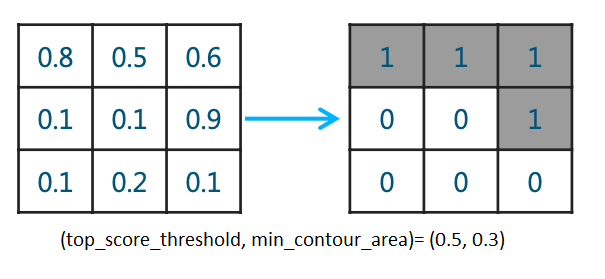

我们训练的分割模型输出每个像素的0-1概率,然后卡一下阈值,我们可以称这样的mask为basic sigmoid mask, 实际上医学图像中我们的分割目标也许并不存在,所以常用双重阈值(top_score_threshold, min_contour_area)的方法计算出mask并同时判断是否有分割目标(在本次比赛中我们分割目标是气胸),这种方法且称为doublet。其具体逻辑为:当大于概率阈值top_score_threshold的pixel数少于

min_contour_area,就将mask像素值全部置0,也就是认为此胸片没有气胸。简单画个示意图如下: